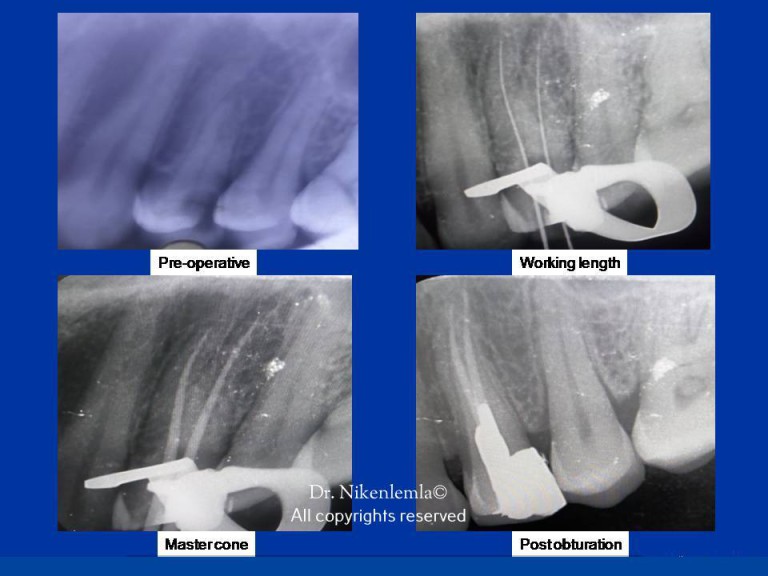

Periapical X Ray

From mavink.com

Periapical X Ray Difference Between Endodontics And Conservative Dentistry They complete an average of. The recent concepts have been highlighted in all the chapters, especially the chapters on dentin hybridization (bonding),. By limiting their practice to endodontics, endodontists focus exclusively on treatments of the dental pulp. Operative dentistry is preventive endodontics. They are different but interconnected phases of. Traditionally, each type of tooth has corresponded to a particular access. Difference Between Endodontics And Conservative Dentistry.